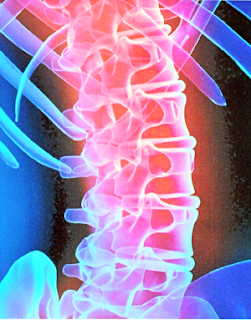

| الشكل 17 يتحكم الحبل الشوكي في رد الفعل |

يُحاط الحبل الشوكي بعظام الفقرات لتحميه ، إلا أنه قد يتعرض للأذى ، و توازي خطورة إصابة الحبل الشوكي خطورة الإصابة في الدماغ ، فقد تسبب الشلل ؛ أي فقدان العضلات قدرتها على الحركة . و تنتج معظم إصابات الرأس و الحبل الشوكي عن حوادث السيارات و الدراجات ، بالإضافة إلى الإصابات الرياضية . لذا فإن وضع حزام الأمان في أثناء القيادة و ارتداء الملابس الواقية في أثناء اللعب و ركوب الدراجة يعد أمراً ضروريًّا .

سهولة الحركة عندما تقوم بحك قطعتي طبشور معاً فإن سطحيهما يتآكلان ، و يتغير شكلاهما . و كذلك فإن العظام دون حماية الغضاريف لها سوف تبدأ في التآكل عند المفاصل . و تساعد الغضاريف على تسهيل حركة المفاصل ؛ حيث تقلل من الاحتكاك ، و تسمح للعظام بالانزلاق بسهولة بعضها فوق بعض . كما في الشكل13 . إن حشوة الغضاريف الموجودة بين فقرات العمود الفقري و المسماة الأقراص تعمل على وسادة تمنع إصابة الحبل الشوكي بالضرر ، كما يعمل السائل الذي يأتي من الأوعية الدموية القريبة على تشحيم المفاصل فيسهل حركتها .

| الشكل 13 صورة أشعة ملونة للعمود الفقري للإنسان تبين الأقراص الغضروفية بين الفقرات . |